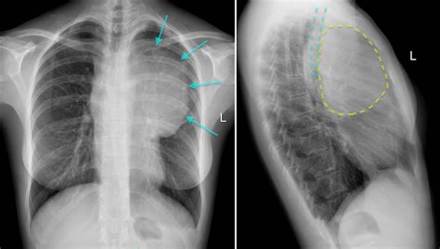

左右纵隔胸膜之间的器官、结构和结缔组织的总称。纵隔呈矢状位,位于胸腔正中偏左,上窄下宽,前短后长。纵隔的前界为胸骨,后界为脊柱胸段,两侧为纵隔胸膜,上界是胸廓上口,下界是膈。正常情况下,纵隔位置较固定。一侧发生气胸时,纵隔向对侧移位。

下纵隔胸骨角平面以下的纵隔部分。上界为上纵隔的下界,下界是膈,左、右侧为纵隔胸膜。下纵隔分3部,心包前方与胸骨体之间为前纵隔,心包连同其包裹的心脏所在部位为中纵隔,心包后方与脊椎胸段之间为后纵隔。

中纵隔位于前、后纵隔之间,容纳心脏及出入心的大血管,如升主动脉、肺动脉干、上腔静脉根部、肺动脉及其分支、左、右肺静脉、奇静脉末端及心包、心包膈动脉、膈神经和淋巴结等。中纵隔是心包囊肿的多发部位。

后纵隔位于心包与脊柱胸部之间,容纳气管杈及左、右主支气管、食管、胸主动脉及奇静脉、半奇静脉、胸导管、交感干胸段和淋巴结等。纵隔内结缔组织及其间隙向上经胸廓上口、向下经主动脉裂孔及食管裂孔,分别与颈部和腹部的结缔组织及其间隙相互延伸,因此纵隔气肿可向上蔓延达颈部,向下蔓延至腹膜后间隙。后纵隔为支气管囊肿、神经瘤、主动脉瘤与膈疝等的多发部位。